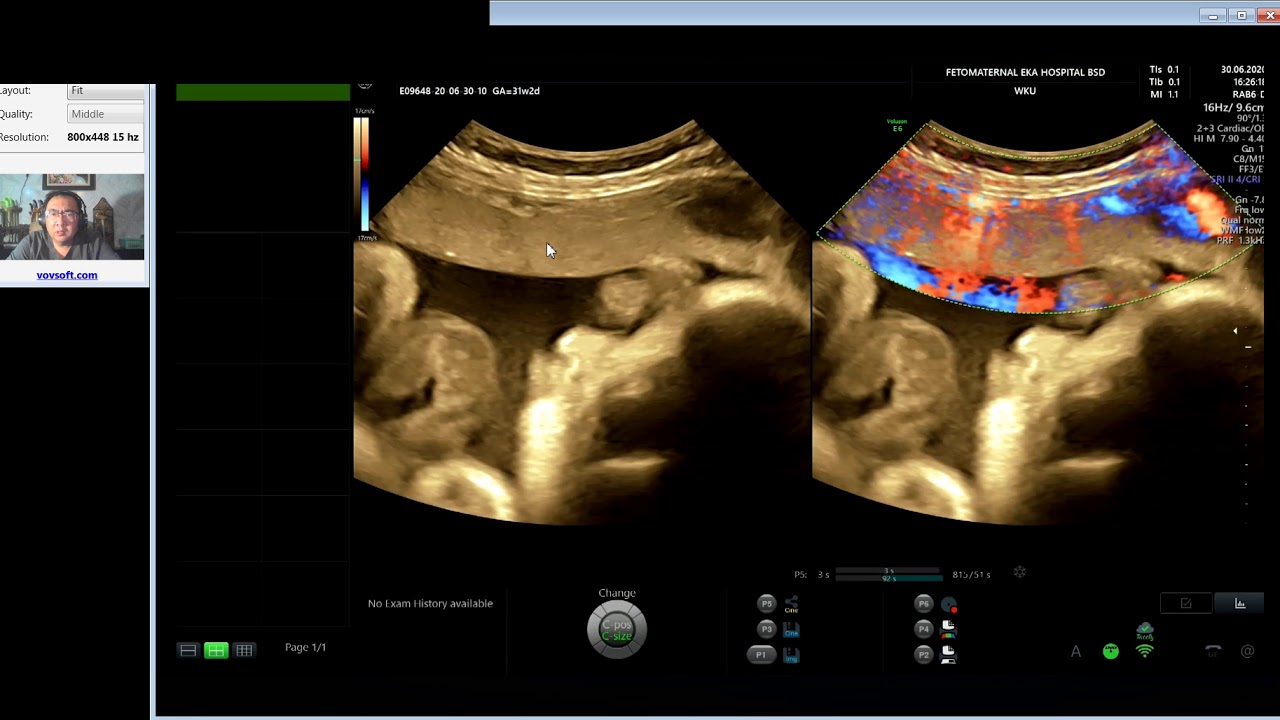

Placenta Akreta Penyebab Kematian Ibu di Era Kini - Tips Hidup Sehat

Narasumber : Dr. Riza Sufriadi, Sp.OG

(Dokter Spesialis Kebidanan dan Penyakit Kandungan RSUD Pijay)

• Plasenta accreta 33 minggu

Plasenta accreta 33 minggu